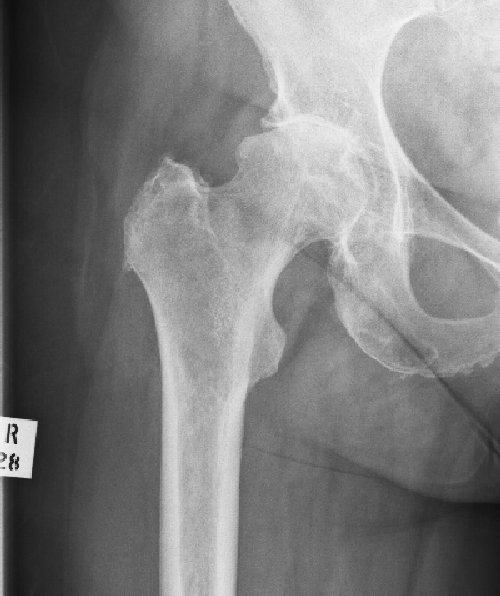

Avascular Necrosis

This is a condition caused by a failure of the blood supply to a part, or the whole, of the femoral head. As the bone is exposed to daily trauma it cannot regenerate and may start to collapse. The extent of the collapse is variable, healing will solidify the head but may lead to a mis-shapen head and therefore early osteoarthritis.

In extreme cases the whole femoral head may fragment and the bone dissolves away.